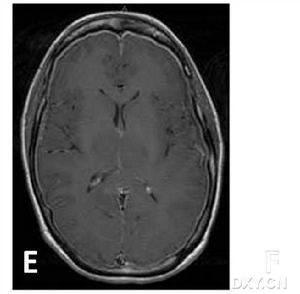

4.少數患者可有意識障礙精神異常及發熱;文獻報導過有失語、偏癱及一過性遺忘等有學者根據病因不同將其分為:原發性顱內低壓綜合徵;術後顱內低壓綜合徵;外傷後顱內低壓綜合徵;腰穿後顱內低壓綜合徵;及腰神經袖撕裂性顱內低壓綜合徵。體格檢查可有輕度頸部抵抗直立時心率減慢,神經系統常無陽性定位體徵腰穿檢查示腦脊液壓力低於70mmH2O,CSF常規化驗檢查多正常。CT或MRI示腦萎縮。以Gd-DTPA增強掃描MRI可顯示全腦硬腦膜瀰漫性強化腦垂直移位

二、輔助檢查:1.CT或MRI常顯示腦萎縮。以Gd-DTPA增強掃描MRI可顯示全腦硬腦膜瀰漫性強化腦垂直移位。2.前庭功能測定也有鑑別診斷意義